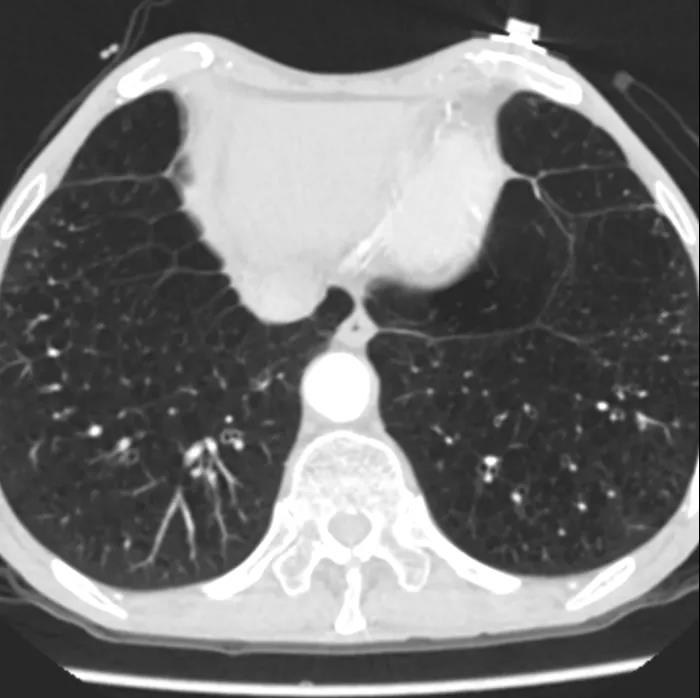

患者男性,66岁,活动后胸闷气促3年,近1年内反复昏厥2次。术前心脏超声提示先天性二叶式主动脉瓣畸形伴重度狭窄、轻度反流,峰值流速4.4m/s,峰值压差89mmHg,平均跨瓣压差57mmHg,瓣口面积0.7cm2,同时心功能差,EF仅30%。CT评估显示主动脉瓣为Type I型二叶瓣,重度钙化,瓣环面积460.4mm2,测算直径24.2mm。左冠脉开口高度14.2mm,右冠脉开口高度13.7mm。患者合并重度肺气肿、多发性肺大泡,且心功能差,STS评分为3.2%,经多学科专家讨论,认为该患者不适合常规开胸外科手术,符合TAVI入组标准。

主动脉瓣瓣环 瓦氏窦

重度肺气肿、多发肺大泡 股动脉入路评估